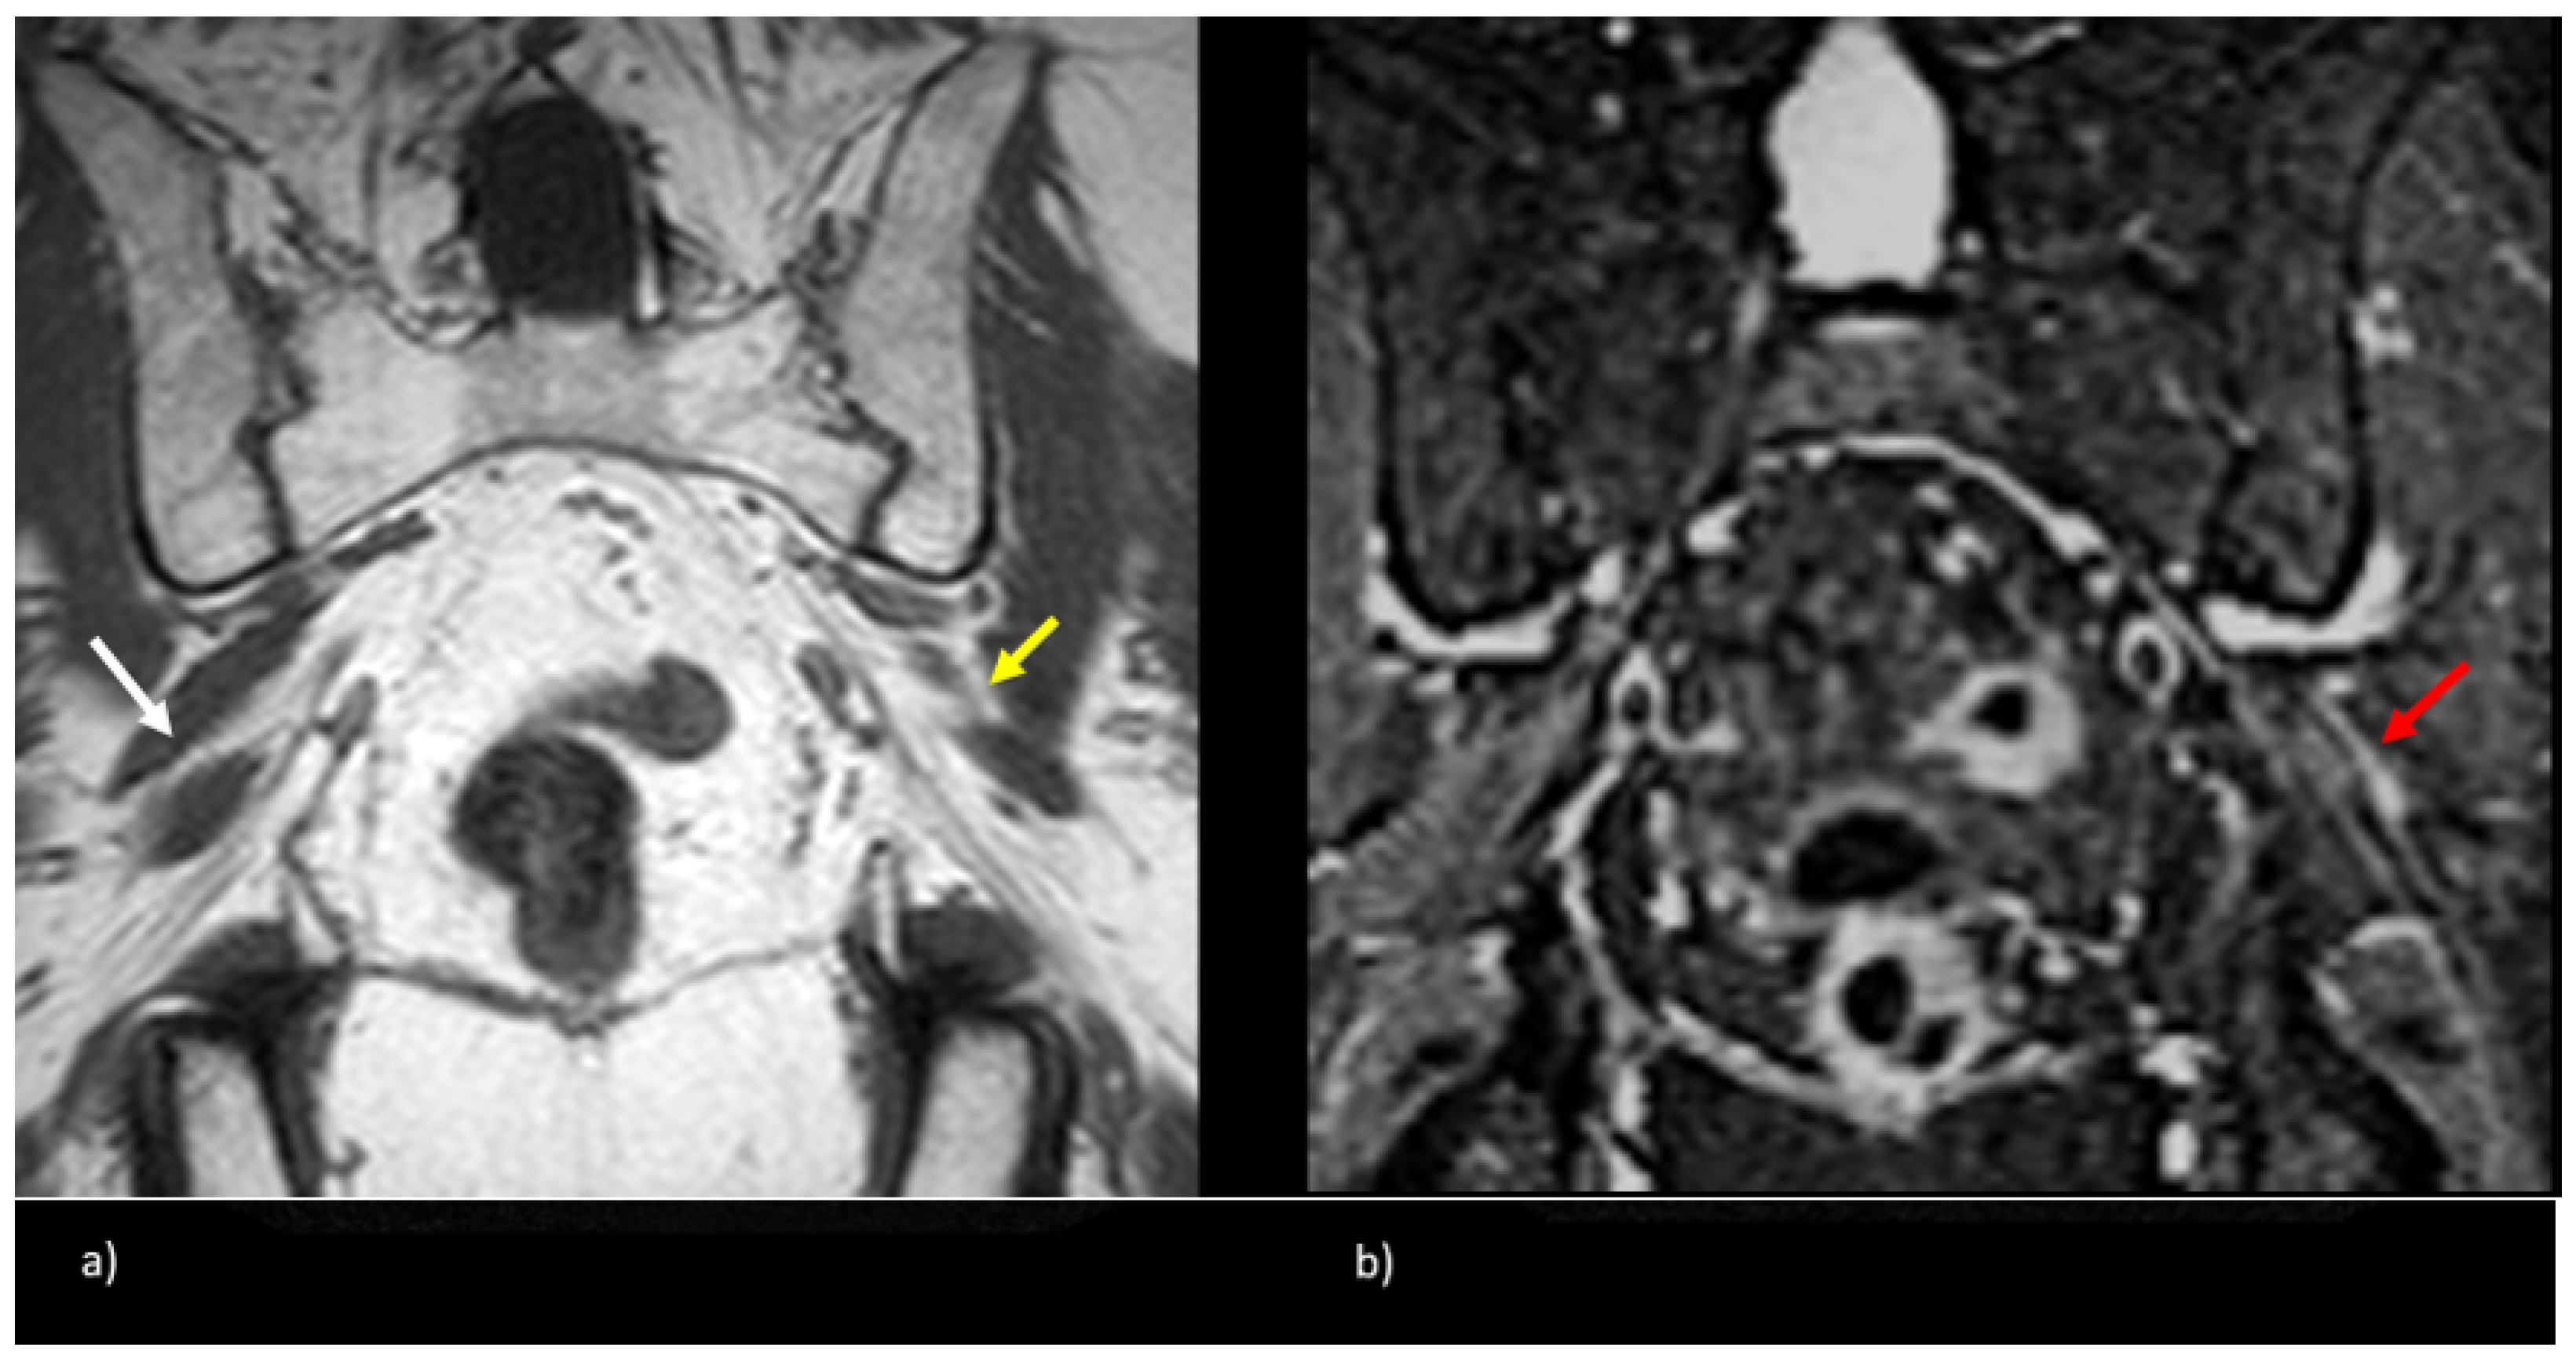

3.2. MR Neurography of the Sciatic Nerves

3.3. Sciatic Nerve Correlation with Findings at MR Neurography